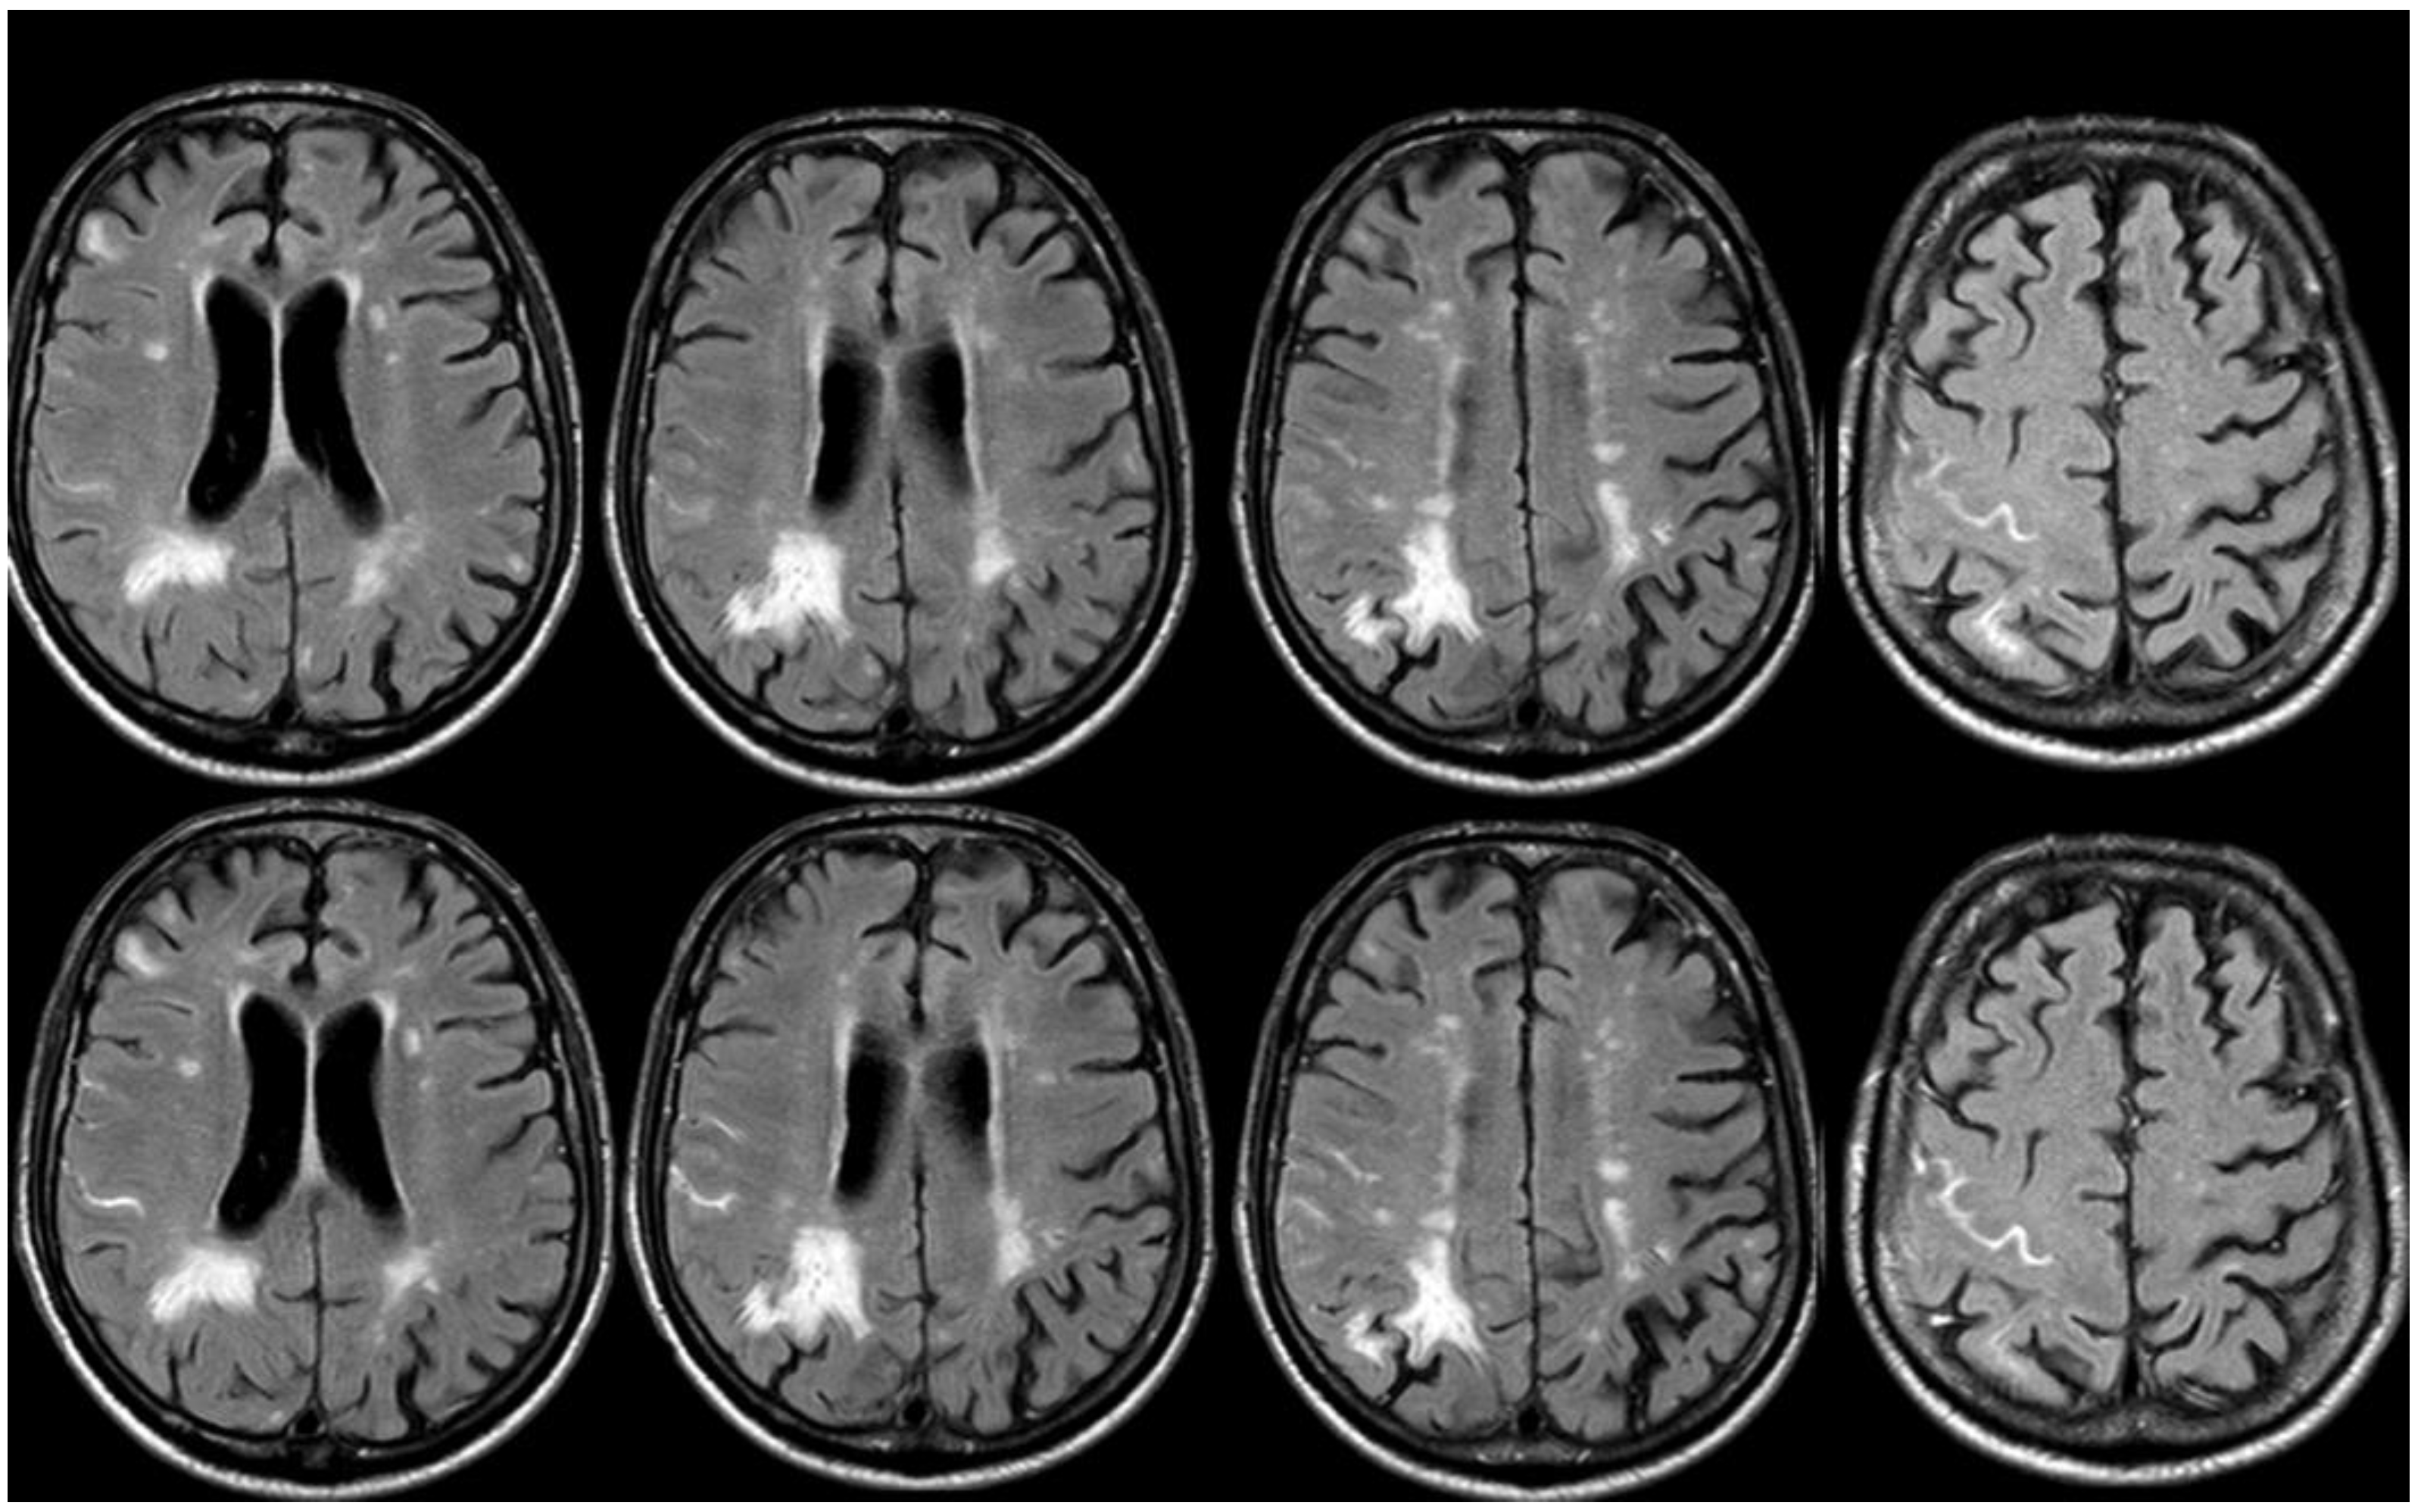

5. February 2017: First Recurrent CAA-Related Inflammation

6. December 2017: Recurrent SAH

7. April 2018: Second Recurrent CAA-Related Inflammation

8. April 2018: Third Recurrent CAA-Related Inflammation